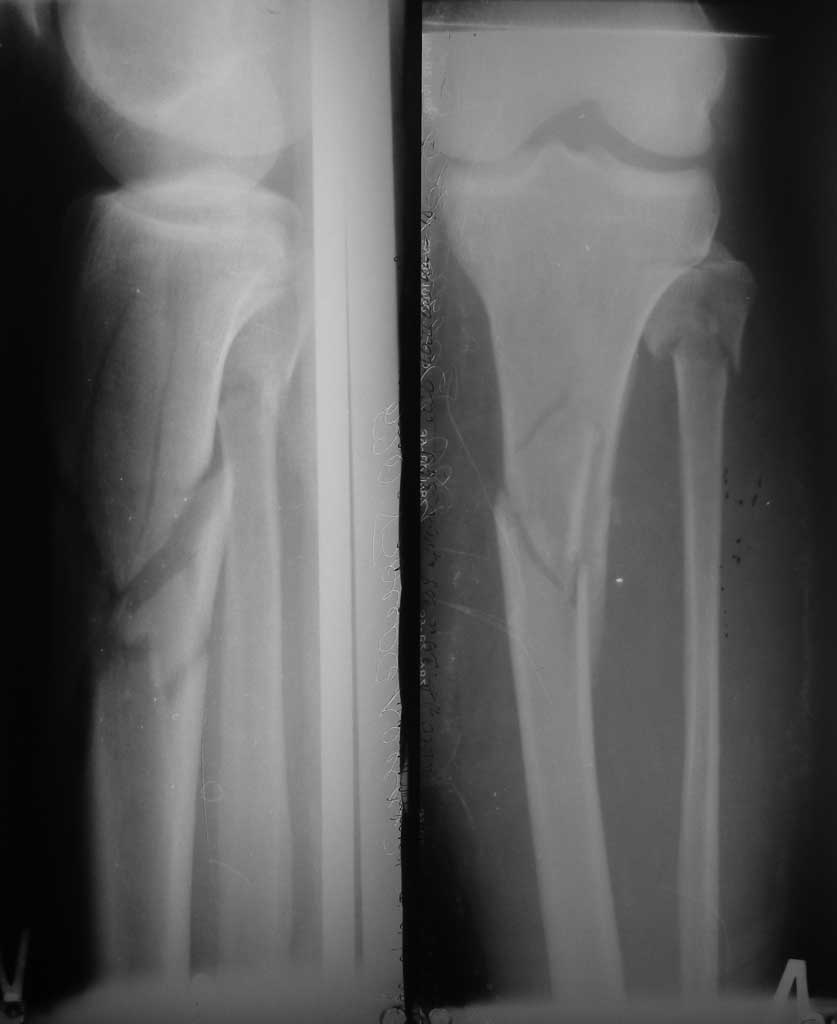

[Ortho] Перелом верхней трети костей голени

День добрый выбран метод лечения мос латеральрой пластиной

ваше мнение ? Целесообразно-ли использование второй стабилизирующей пластины?Прошу вас, ответьте на это сообщение в кротчайшие сроки. Очень нужна ваша помощь.